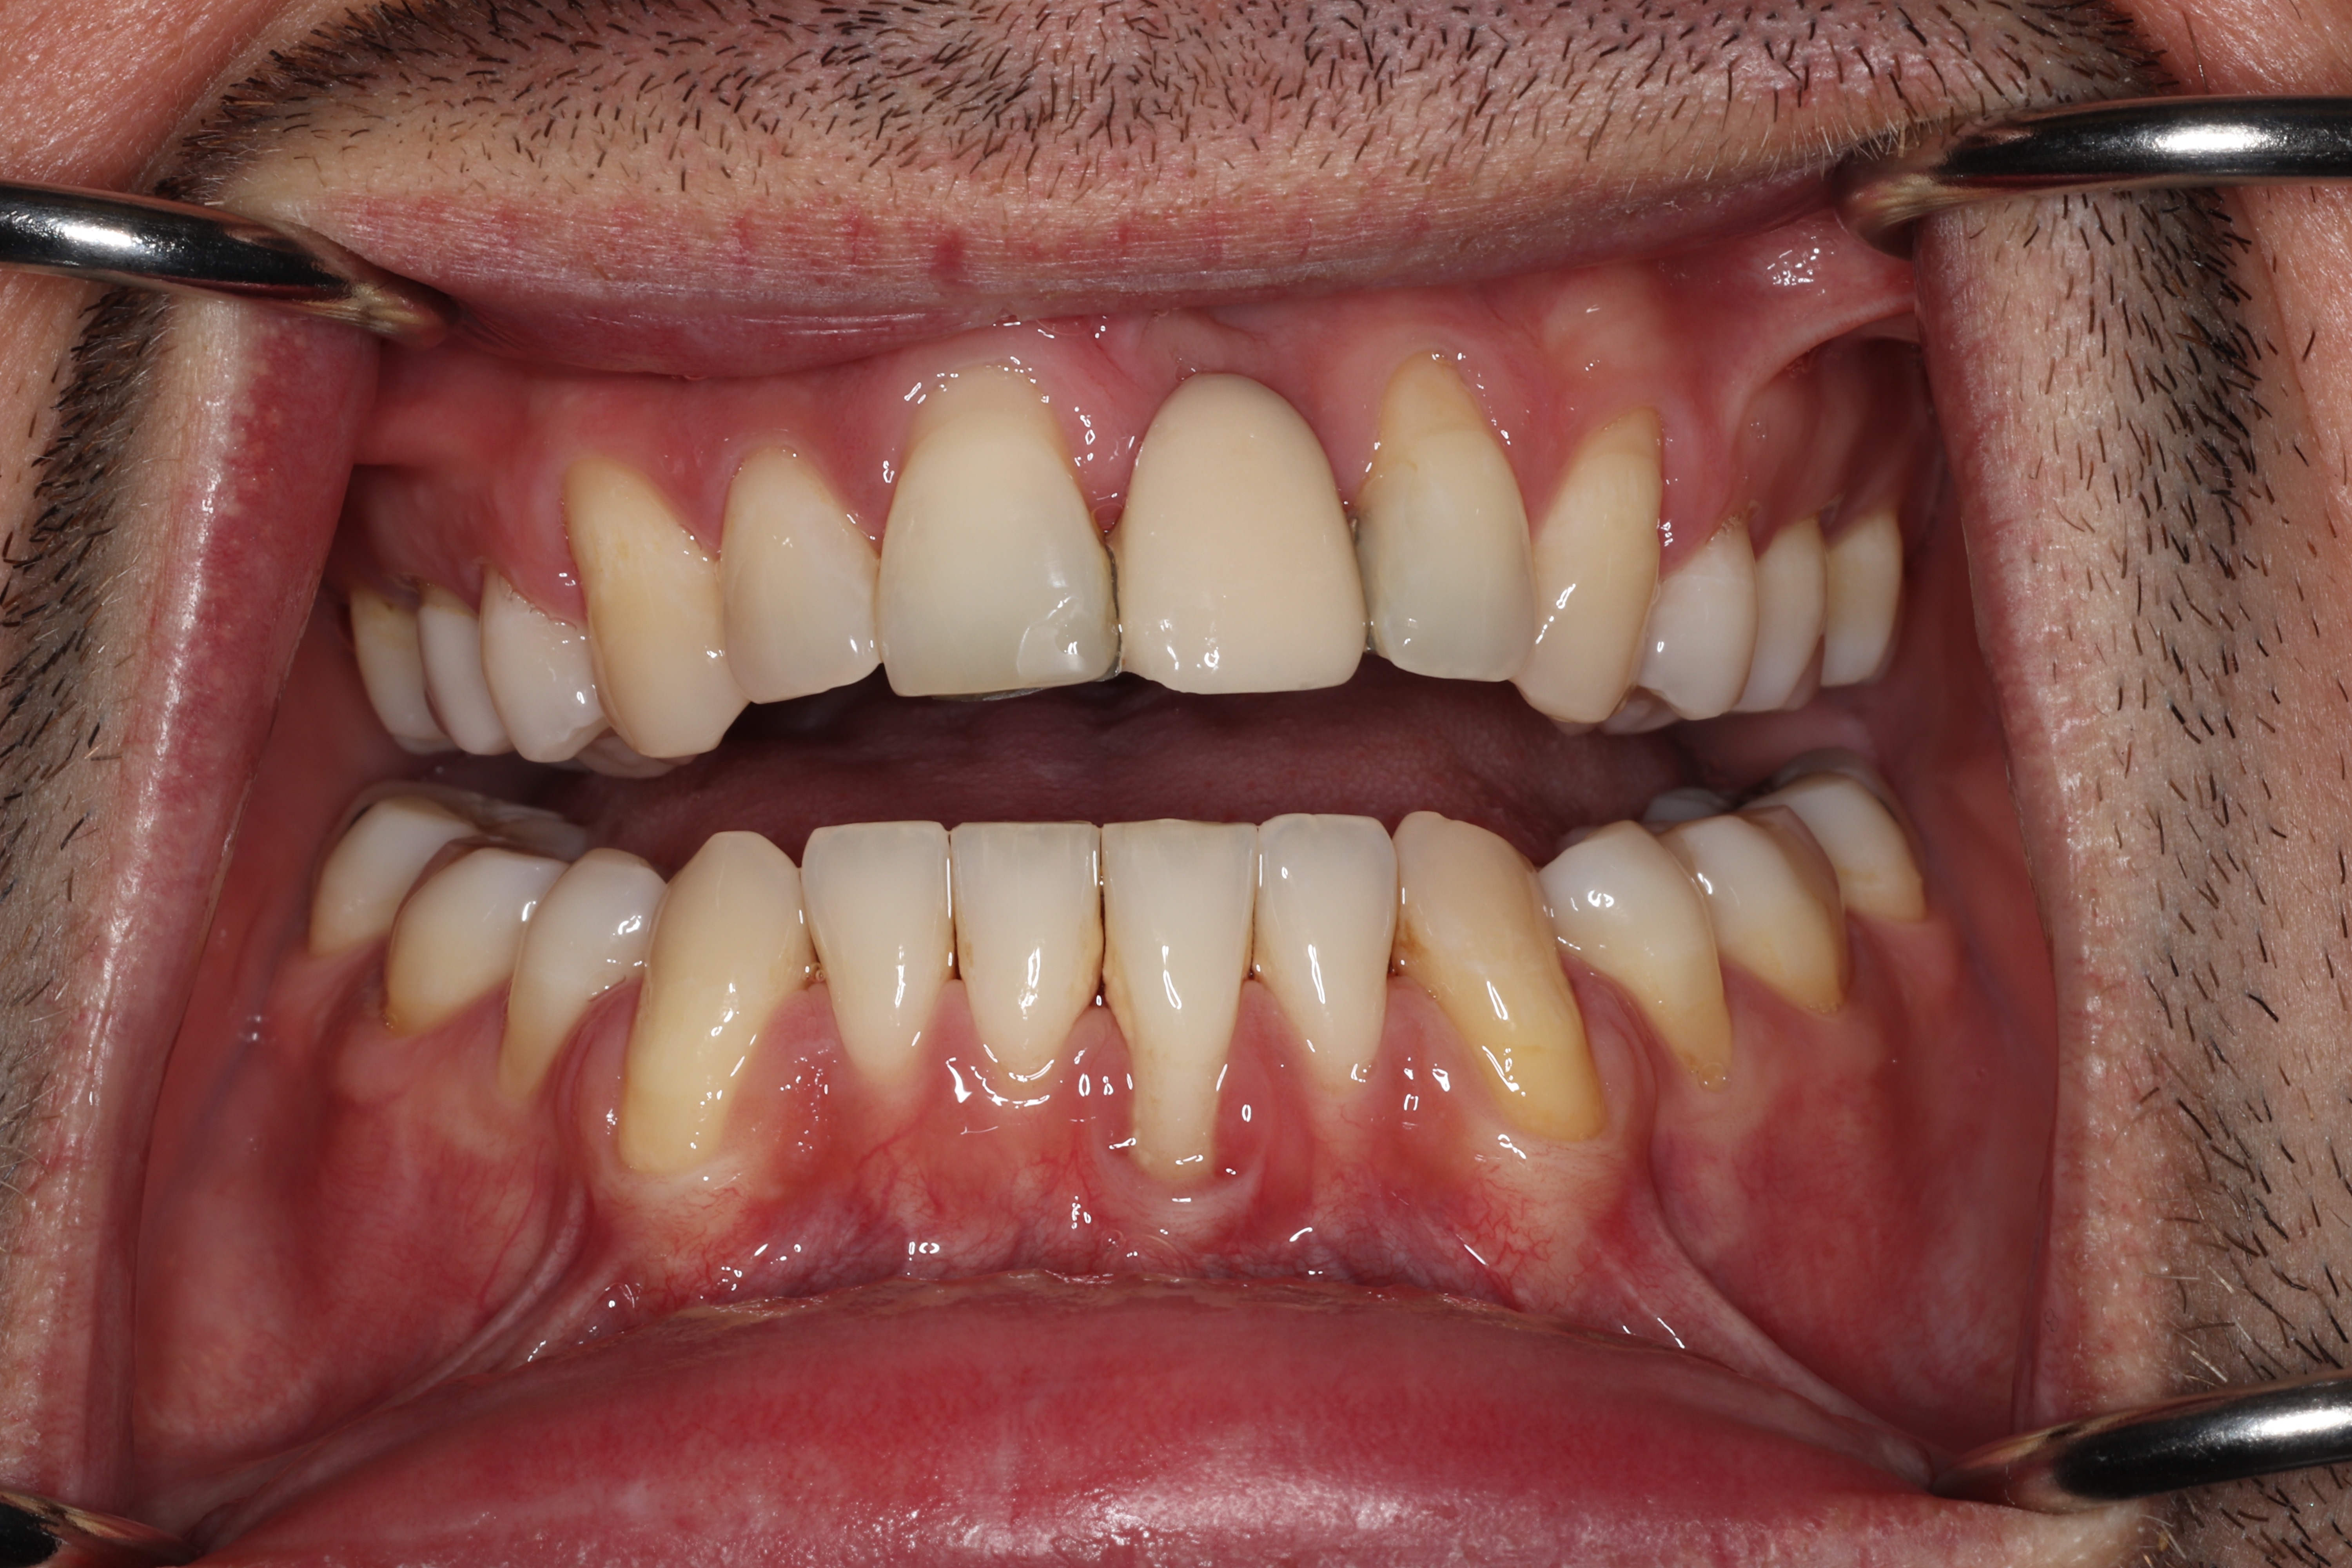

This patient has healthy thick gum tissue. The free gingiva is the cuff surrounding the tooth and the attached gingiva is the thick tissue attached to the bone. Both of these are made of keratinized tissue.

This patient is lacking all keratinized tissue. They only have thin alveolar mucosa surrounding their teeth which is leading to both recession and bone loss.

Take a closer look at the difference between the two areas in this patient's mouth. The teeth surrounded by thick, firmly attached protective tissue show no plaque buildup, no inflammation, and stable, healthy gum levels. In contrast, the sites that lack this protective tissue are visibly inflamed and collecting bacteria along the gumline, which is driving progressive recession. Without intervention to rebuild that protective barrier through grafting, the affected teeth would continue to lose gum tissue and bone support over time, ultimately putting them at risk of being lost entirely.